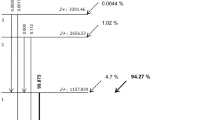

Effect of MRI-based PET AC

The atlas-based MRI AC of the PET data yielded reference PET values in the tumor with a SUVmax of 25 g/ml. The tumor was located at the base of the tongue with a size of 2.3 × 3.7 × 3 cm. The distance between the hottest voxel within the tumor and the center of the artifact was 5 mm. The absolute and relative change of SUVmax with increasing diameters of the artificial artifact is given in Table 4. While a signal void of 0.5 cm did not cause any significant change (−0.1%), 5 cm led to substantial underestimation of tumor activity of −33% in our selected case (Figure 4).

The isocontour maps illustrating the percentage difference from baseline in each area of the image are given for three cases with increasing artifact sizes from 0.5 to 5 cm (Figure 5).

Different views of the baseline PET image and isocontour plots. (a) Axial, coronal, and sagittal views of the baseline PET image, corrected with the MR atlas without signal void. (b-d) Axial, coronal, and sagittal views of the isocontour plots illustrating the relative difference (from 0% to 50%), between the baseline PET and reconstructed PET images with artificial signal voids with increasing sizes (B = 0.5, C = 2.5, and D = 5 cm).